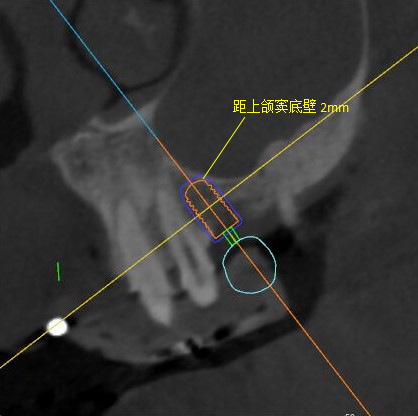

矢狀面視圖

根據(jù)患者CT顯示,使用種植導(dǎo)航軟件設(shè)術(shù)前手術(shù)方案??紤]到患者拒絕手術(shù)摘除上頜竇囊腫等因素,此次手術(shù)選用了Straumann骨水平4.10*8.0mm的植體,植體末端位點(diǎn)設(shè)計(jì)距上頜竇底壁2mm處的同時(shí)兼顧種植方向和修復(fù)間隙,來(lái)達(dá)到理想的效果。